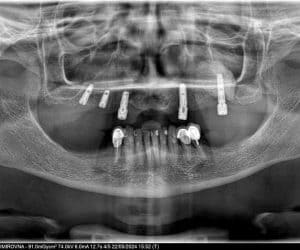

Коронки керамические с опорой на имплантатах

Цель визита пациента

- Пациентка Екатерина посетила нашу клинику с целью проведения процедуры установки имплантатов для восстановления функциональности и эстетики зубного ряда

Детали лечебного процесса

- После проведенной консультации и рентгенологического обследования были установлены 5 имплантатов. Через 2 месяца, после остеоинтеграции имплантатов, были установлены керамические коронки в 1 визит.

Продолжительность и этапы лечения

- 2 месяца

- 3 визита